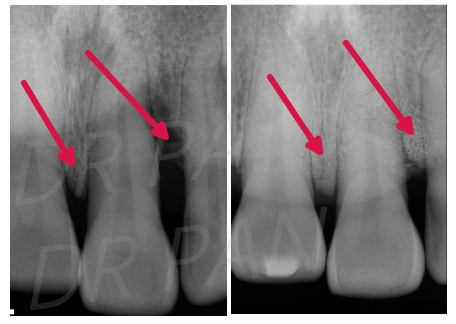

再生手术所耗费的时间较长,往往需要3-6个月供新骨头形成、生长。

电刀怎么洗我以为只要洗个牙,医生你怎么还拿起了手术刀?_https://www.jmylbn.com_新闻资讯_第8张

再生手术前后